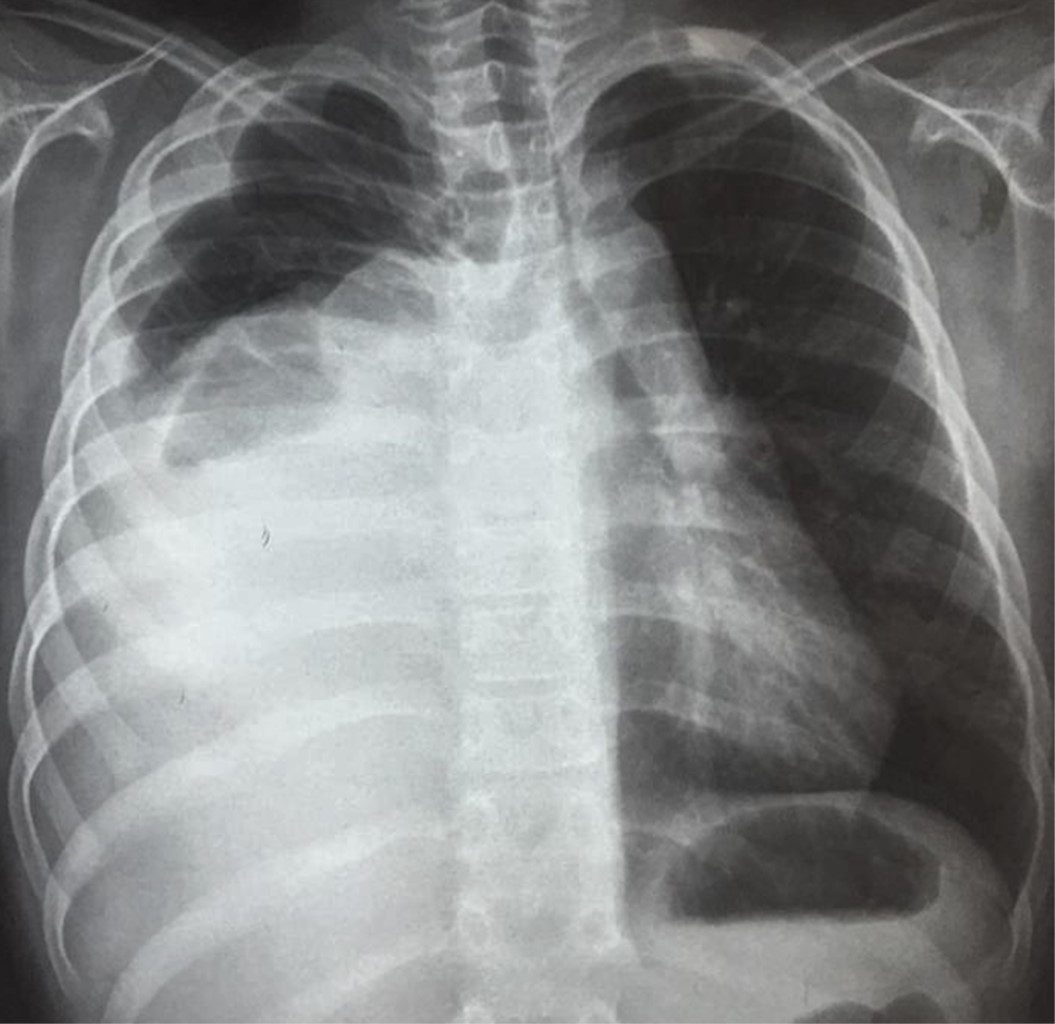

La recuperación posoperatoria transcurrió sin incidentes. Ingresó en la unidad de cuidados intensivos para manejo hemodinámico, se retira ventilación asistida 10 horas después de la operación, la radiografía de tórax control demostró expansión pulmonar completa (Figura 5). Los resultados histopatológicos revelaron un tumor germinativo mixto con componente de teratoma maduro en 70% y teratoma inmaduro en 30%. Fue dado de alta a las dos semanas posoperatorias sin ninguna complicación. Actualmente se encuentra en seguimiento oncológico por la consulta de especialidades.